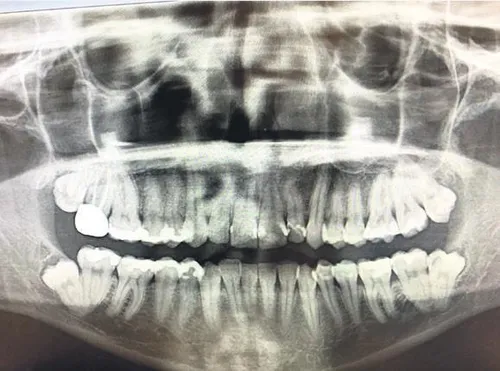

Geçen her gün, hafta, ay veya yıl; hastanın odaklanmış enfeksiyon ile mücadele eden bağışıklık sistemine yük bindirmektedir ve bu gerçekten hiç güvenli değildir. Ağızdaki enfeksiyonu kontrol altına almak için tekrarlanan antibiyotikler de ayrıca bağırsaktaki iyi bakterilerin ölümüne, mikrobiyomun çalışmamasına ve bundan ötürü bağırsakta problem riskinin doğmasına sebep olur. Aşırı antibiyotik kullanımı, zararlı bakterilerin antibiyotiklere karşı direncini artırır. Diş hekimleri, kök kanallarının dijital görsellerini dikkatlice incelemeli ve olası enfeksiyonun işaretlerini aramalıdır. Kök kanalı enfeksiyonlu ise onun vücuttan çıkarılması gerekir.

Kronik ağız enfeksiyonları çok çeşitli hastalıklar yolu ile sağlığınız için risk oluşturabilir. En başta felç ve kardiyovasküler problemlere yol açabilir. Fakat bunlarla birlikte romatoit artrit, şeker hastalığı, solunum enfeksiyonları, kanser ve doğum problemleri gelir. Eğer bir kök kanalınız varsa ve bu problemleri yaşıyorsanız, kök kanalının çeneye bağlı olduğu yerinde enfeksiyonlu olmadığına emin olmalısınız. Eğer enfeksiyon varsa kontrol etmesini bilen bir hekime başvurmalısınız, çünkü dediğim gibi çenedeki bir enfeksiyon gözle görülemeyebilir.